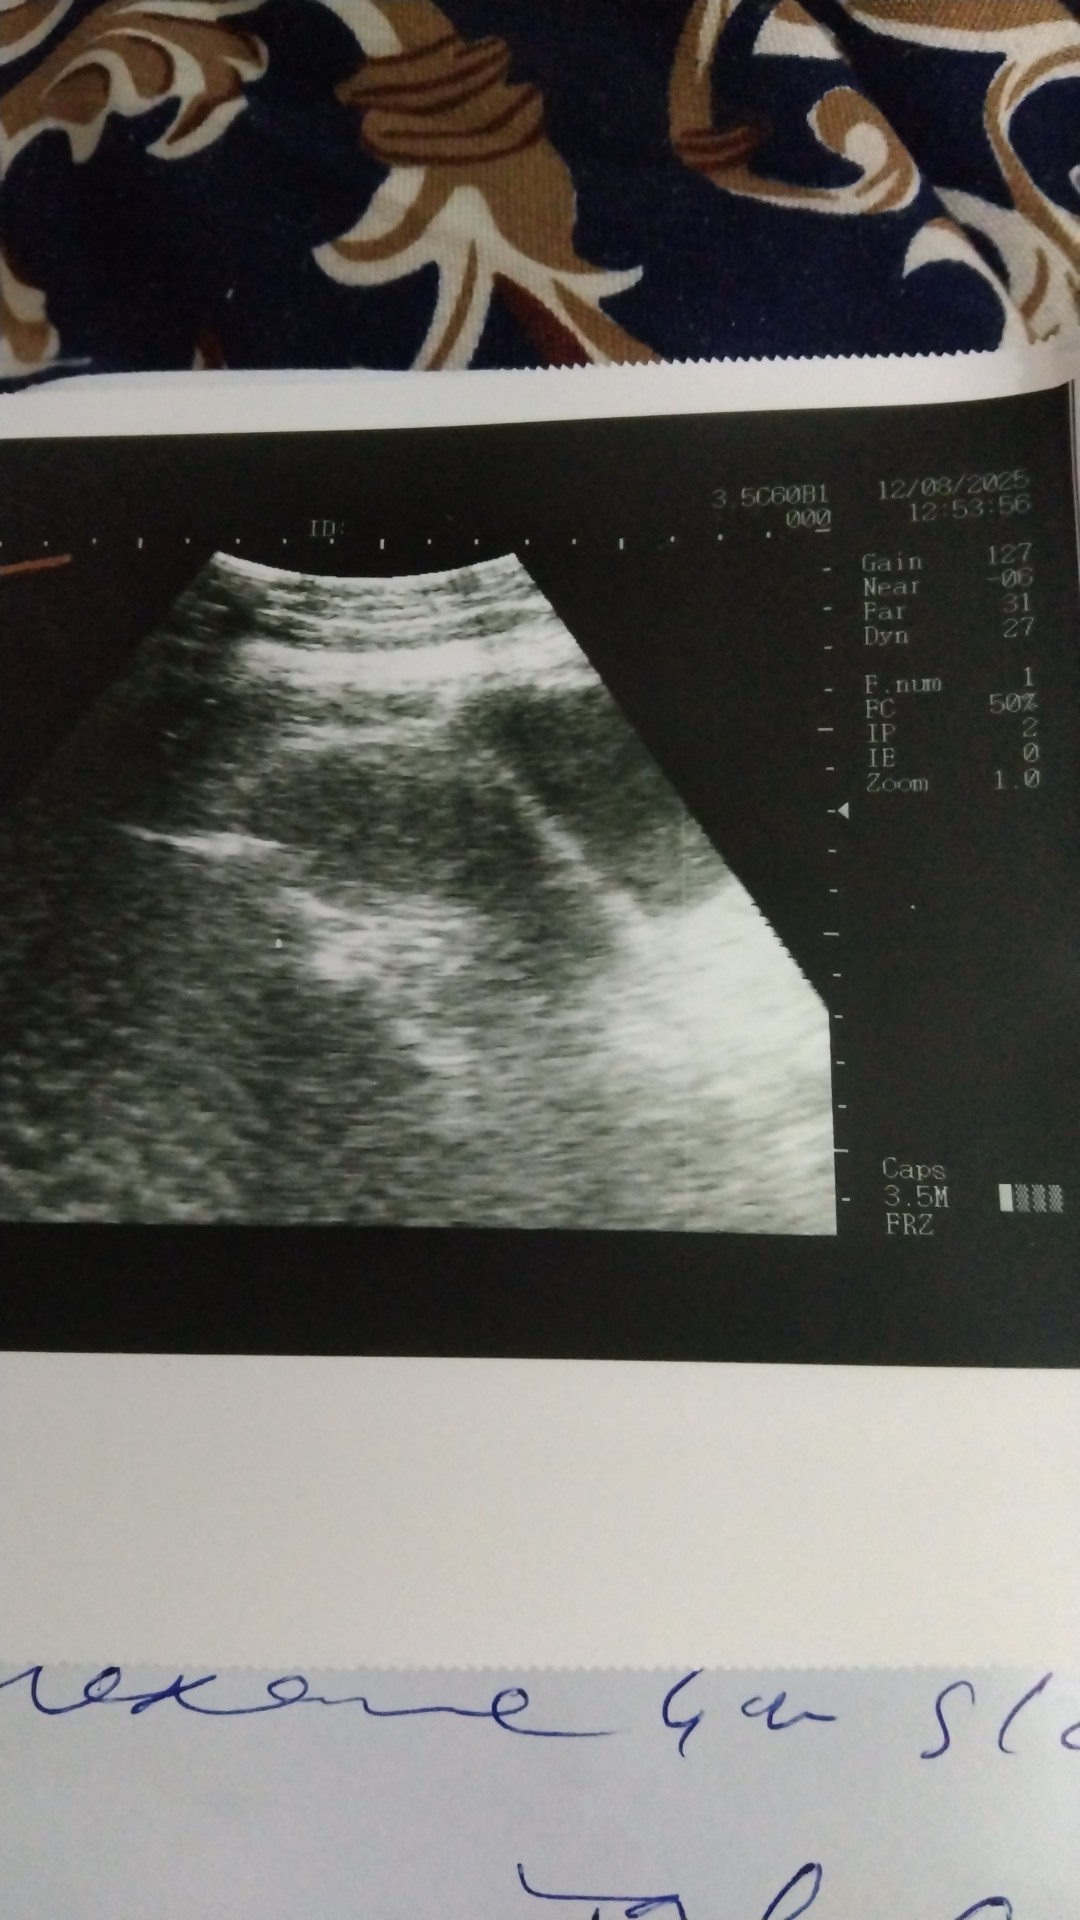

Kindly read and tell pregnancy is exit or not according to this ultrasound

I mean to say mjy pregnancy h ya ni according to this ultrasound

This is not clear picture , get your beta hcg test done

this shows uterus is clear in this view